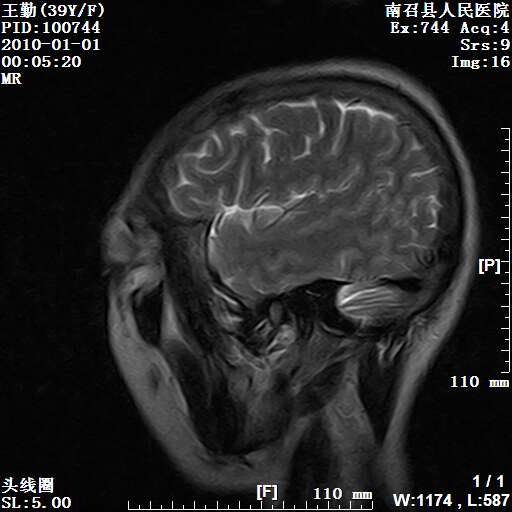

以下是引用随光逐影在2010-1-22 9:03:00的发言:[br]考虑左侧中颅窝(蝶骨翼区)脑膜瘤侵犯蝶骨翼并突入左侧眼眶。

以下是引用水过无痕在2010-1-22 14:55:00的发言:[br]一、定位:颅外占位;二、定性:恶性可能性大;三、组织来源:来源于左侧眼外直肌或其他部位;考虑为:横纹肌肉瘤>转移瘤>脑膜瘤.